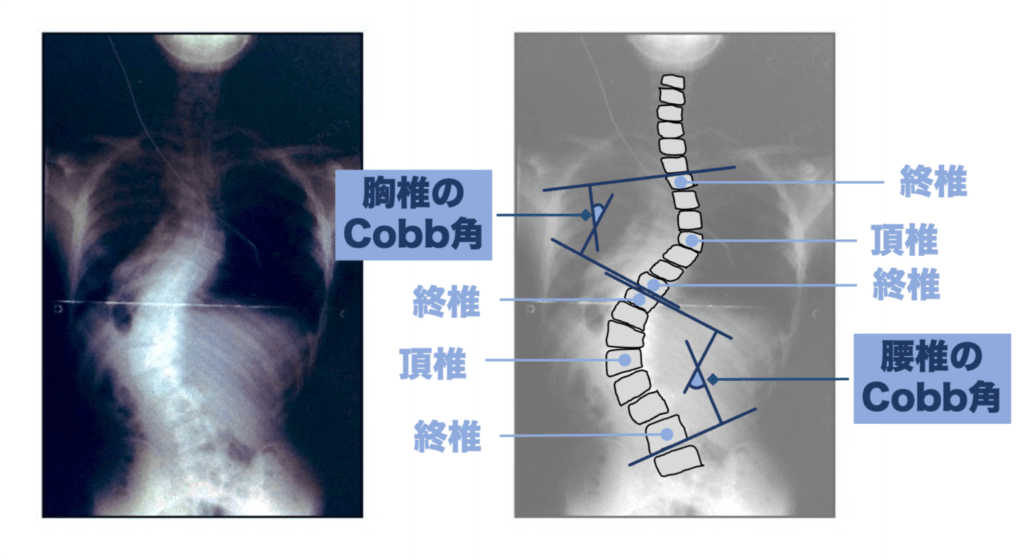

これらの治療方針を決める判断材料のひとつがコブ角と呼ばれるものです。

これは側弯症の弯曲(カーブ)の大きさを示したものです。

つまり、コブ角は側弯症の重症度とも言えます。

そして、手術に踏み切るのはコブ角が45°を超えてきたタイミングが多くなります。